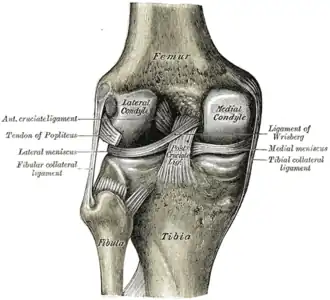

![]() Правый коленный сустав, сбоку. | |

![]() Левый коленный сустав сзади, показаны внутренние связки. | |

Передний и латеральный вид колена.